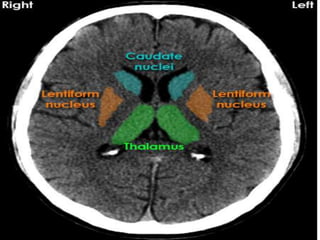

Anatomical Land marks.

• Subcortical structures including basal

ganglia,thalamus .

Anatomical Land marks. •Cortex and division into various lobes. • Subcortical structures including basal ganglia,thalamus . • Pituatry area and cavernous sinus region. • Brainstem. • CSF system. • Arterial and venous system.